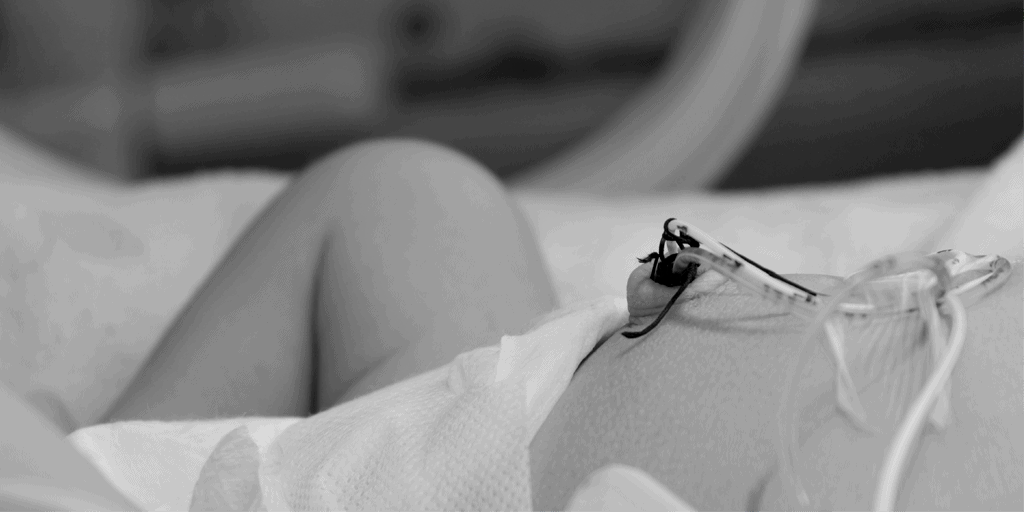

El uso del cateterismo umbilical es una práctica usual en las unidades de cuidados intensivos neonatales. Su aplicación en la atención a recién nacidos ha ido variando y ajustándose a las demandas de los pacientes y al desarrollo de nuevas tecnologías y procedimientos en el campo de los cuidados neonatales.

En este ebook encontrarás una recopilación de artículos publicados en nuestro blog con los protocolos para la elección y manipulación de catéteres umbilicales en recién nacidos.